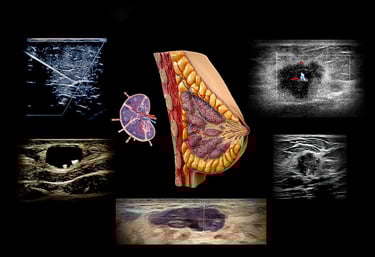

Every concept is explained in plain, practical language—anatomy, physics, instrumentation, Doppler, and pathology—so you always understand why you’re doing something before we show you how to do it. Then, nearly every minute is devoted to hands-on scanning with real-time, individual guidance that builds a repeatable breast imaging workflow you can trust in any clinical setting.

Breast imaging demands precision with sensitivity—clinical and interpersonal. This hands-on course matters because it teaches you to quietly detect subtle change and discern between benign and concerning patterns in a structured, guided setting.

You’ll refine image acquisition, Doppler assessment, and interpretation strategies that allow you to make confident clinical calls and communicate them effectively to patients and care teams.

Understand the “why” behind image and Doppler findings with easy-to-grasp physics explanations